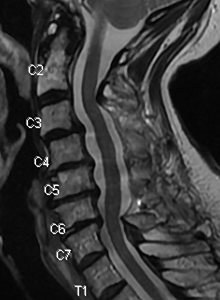

Elderly lady presents with difficulty using her hands. She cannot button her shirt and when she walks she feels like she is going to fall. Her MRI shows spinal cord compression (myelopathy). A side view shows the narrowing of the spinal canal. The cross section (middle picture) show the spinal cord compressed compared to a normal cross section (right).